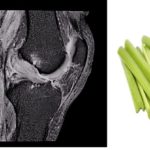

The Double PCL Sign on MRI is a feature of

The celery stalk sign is classic of A. Hoffa Fat pad inflammation B. Mucoid Degeneration…